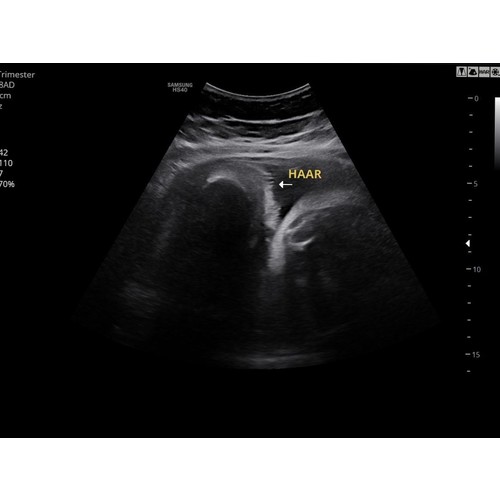

Hier ook haartjes van 3 cm lang gezien op de groei echo met 35 weken .. ben benieuwd straks 😊